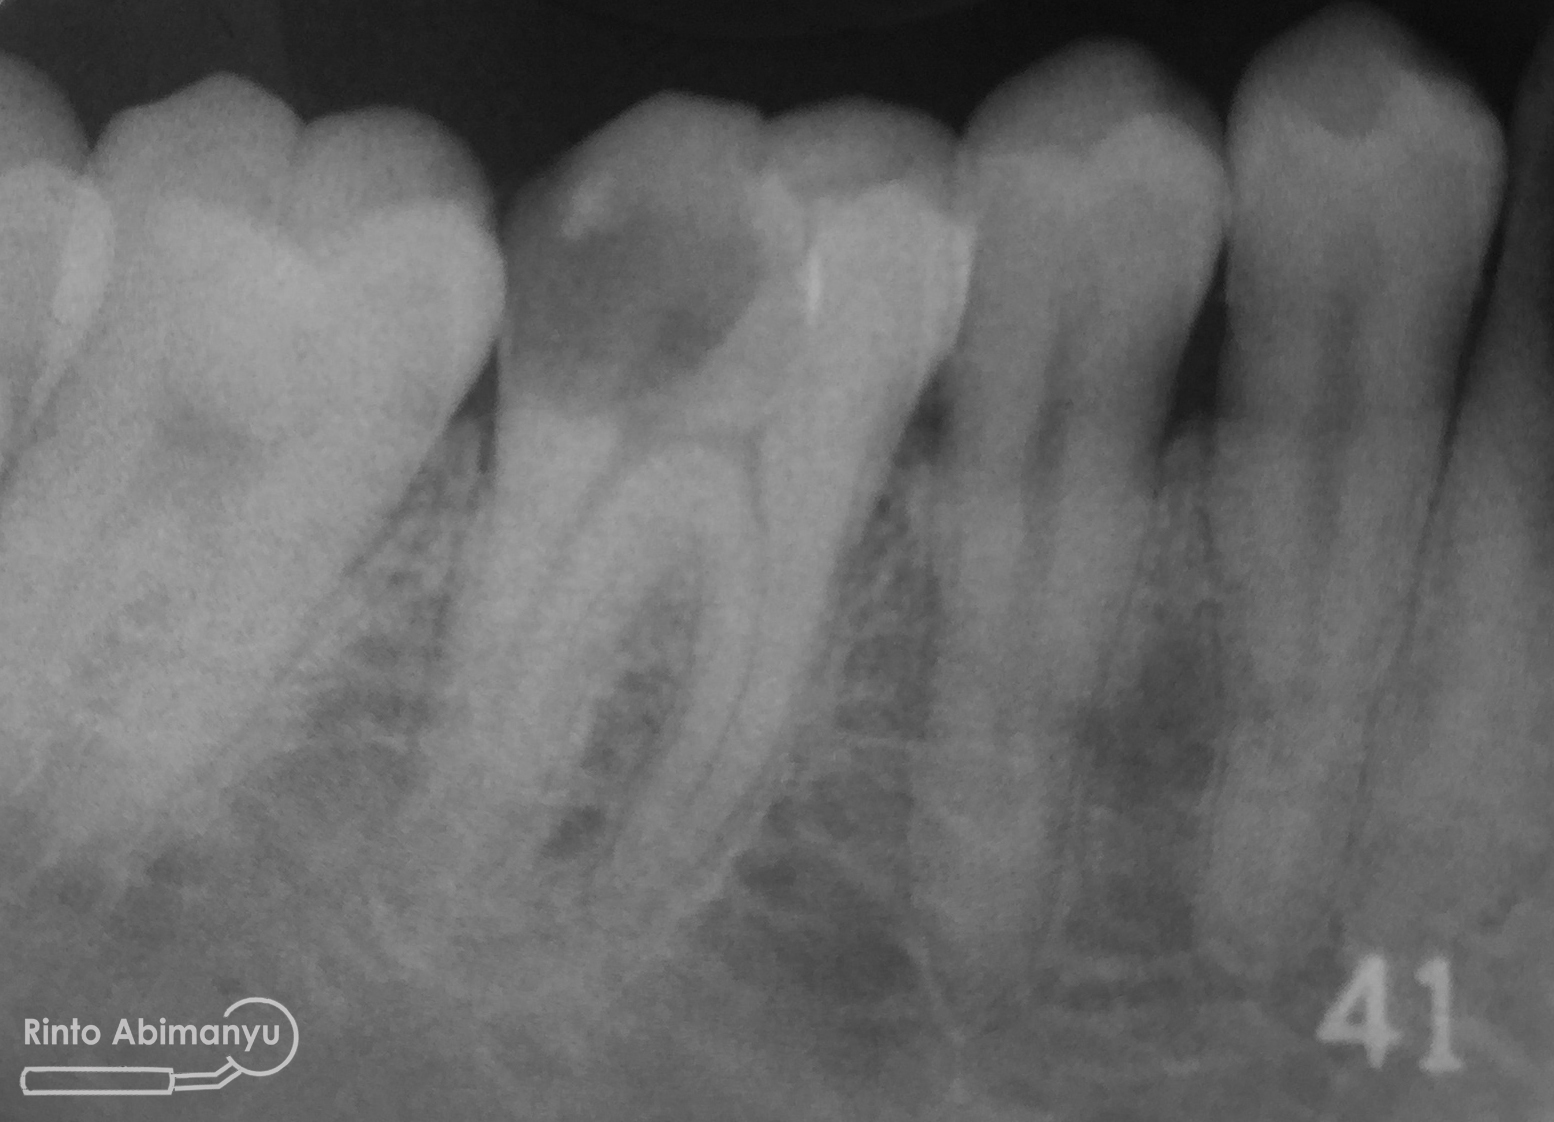

Kemudian dilakukan foto ronsen gigi tersebut…

Terlihat kavitas sudah mengenai kamar pulpa, dan dari hasil tes respon dingin serta tes perkusi menunjukkan hasil negatif… Kondisi yang saya temukan diinfokan ke pasien dan dijelaskan rencana perawatan untuk giginya, setelah pasien mengerti dan menyatakan setuju perawatan baru dimulai…